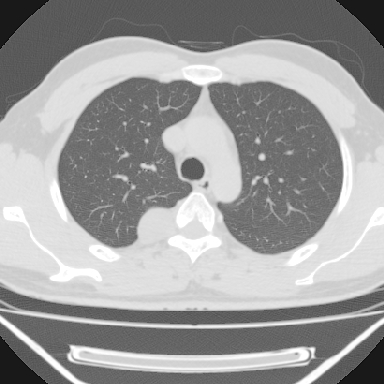

m 30 右胸痛10年

右上后纵隔脊柱旁类圆形肿块,边界光整,与胸腔呈钝角,首先考虑来源于肺外,神经源性肿瘤(神经鞘瘤可能大,神经鞘瘤)

右上后纵隔旁软组织肿块影,与肺界面光滑,与胸壁呈钝角相交,提示肺外病变。位于肋骨下缘,边缘清楚,呈三角样指向与右侧椎间孔,但并示进入椎间孔;与对侧神经根对比,属同一走行方向。

考虑后纵膈良性肿瘤,神经源性肿瘤可能大。

鉴别:胸膜来源肿瘤。影像表现虽有肺外征象,但无胸水等相应佐证;再者,病史前10年,超长,与胸膜肿瘤不太吻合。

建议:再次查体,问清疼痛部位,如为1~2个肋间痛则神经源性肿瘤可能大,如疼痛较弥散,不按肋间分布,则可能为后纵膈其它来源肿瘤。

右上后纵隔脊柱旁见长椭圆形肿块,边界光整,与胸壁呈钝角。周围骨质未见异常。

考虑、1、后纵隔神经源性肿瘤;

2、不除外单发胸膜间皮瘤。